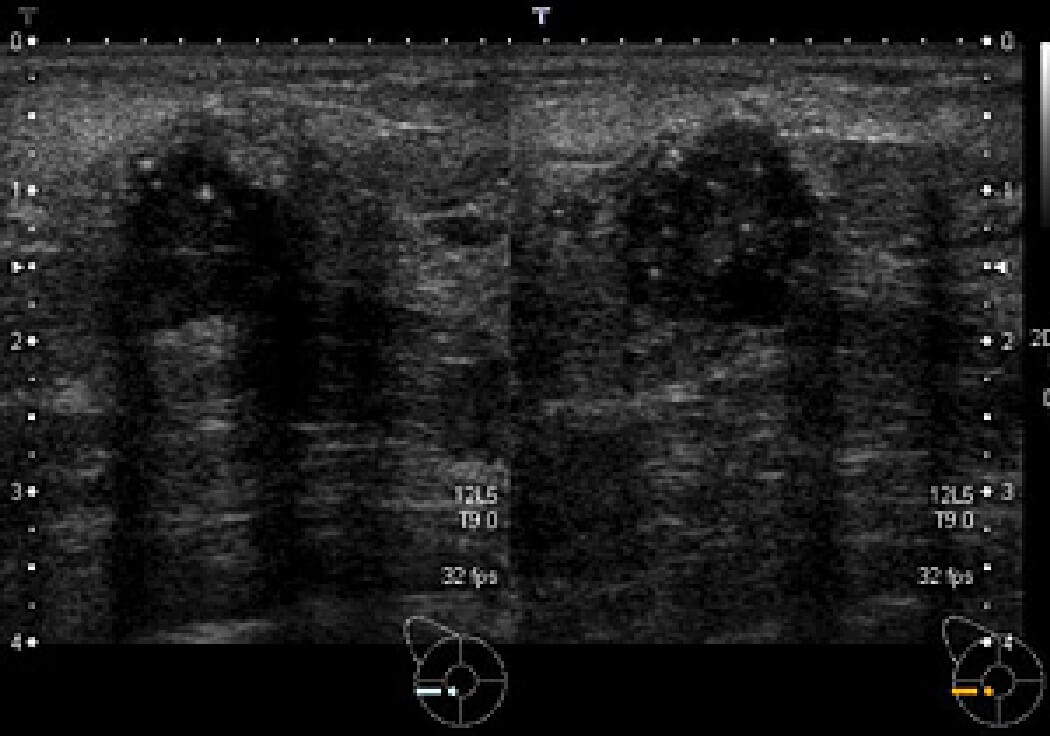

乳房超音波検査

乳がんの症例1